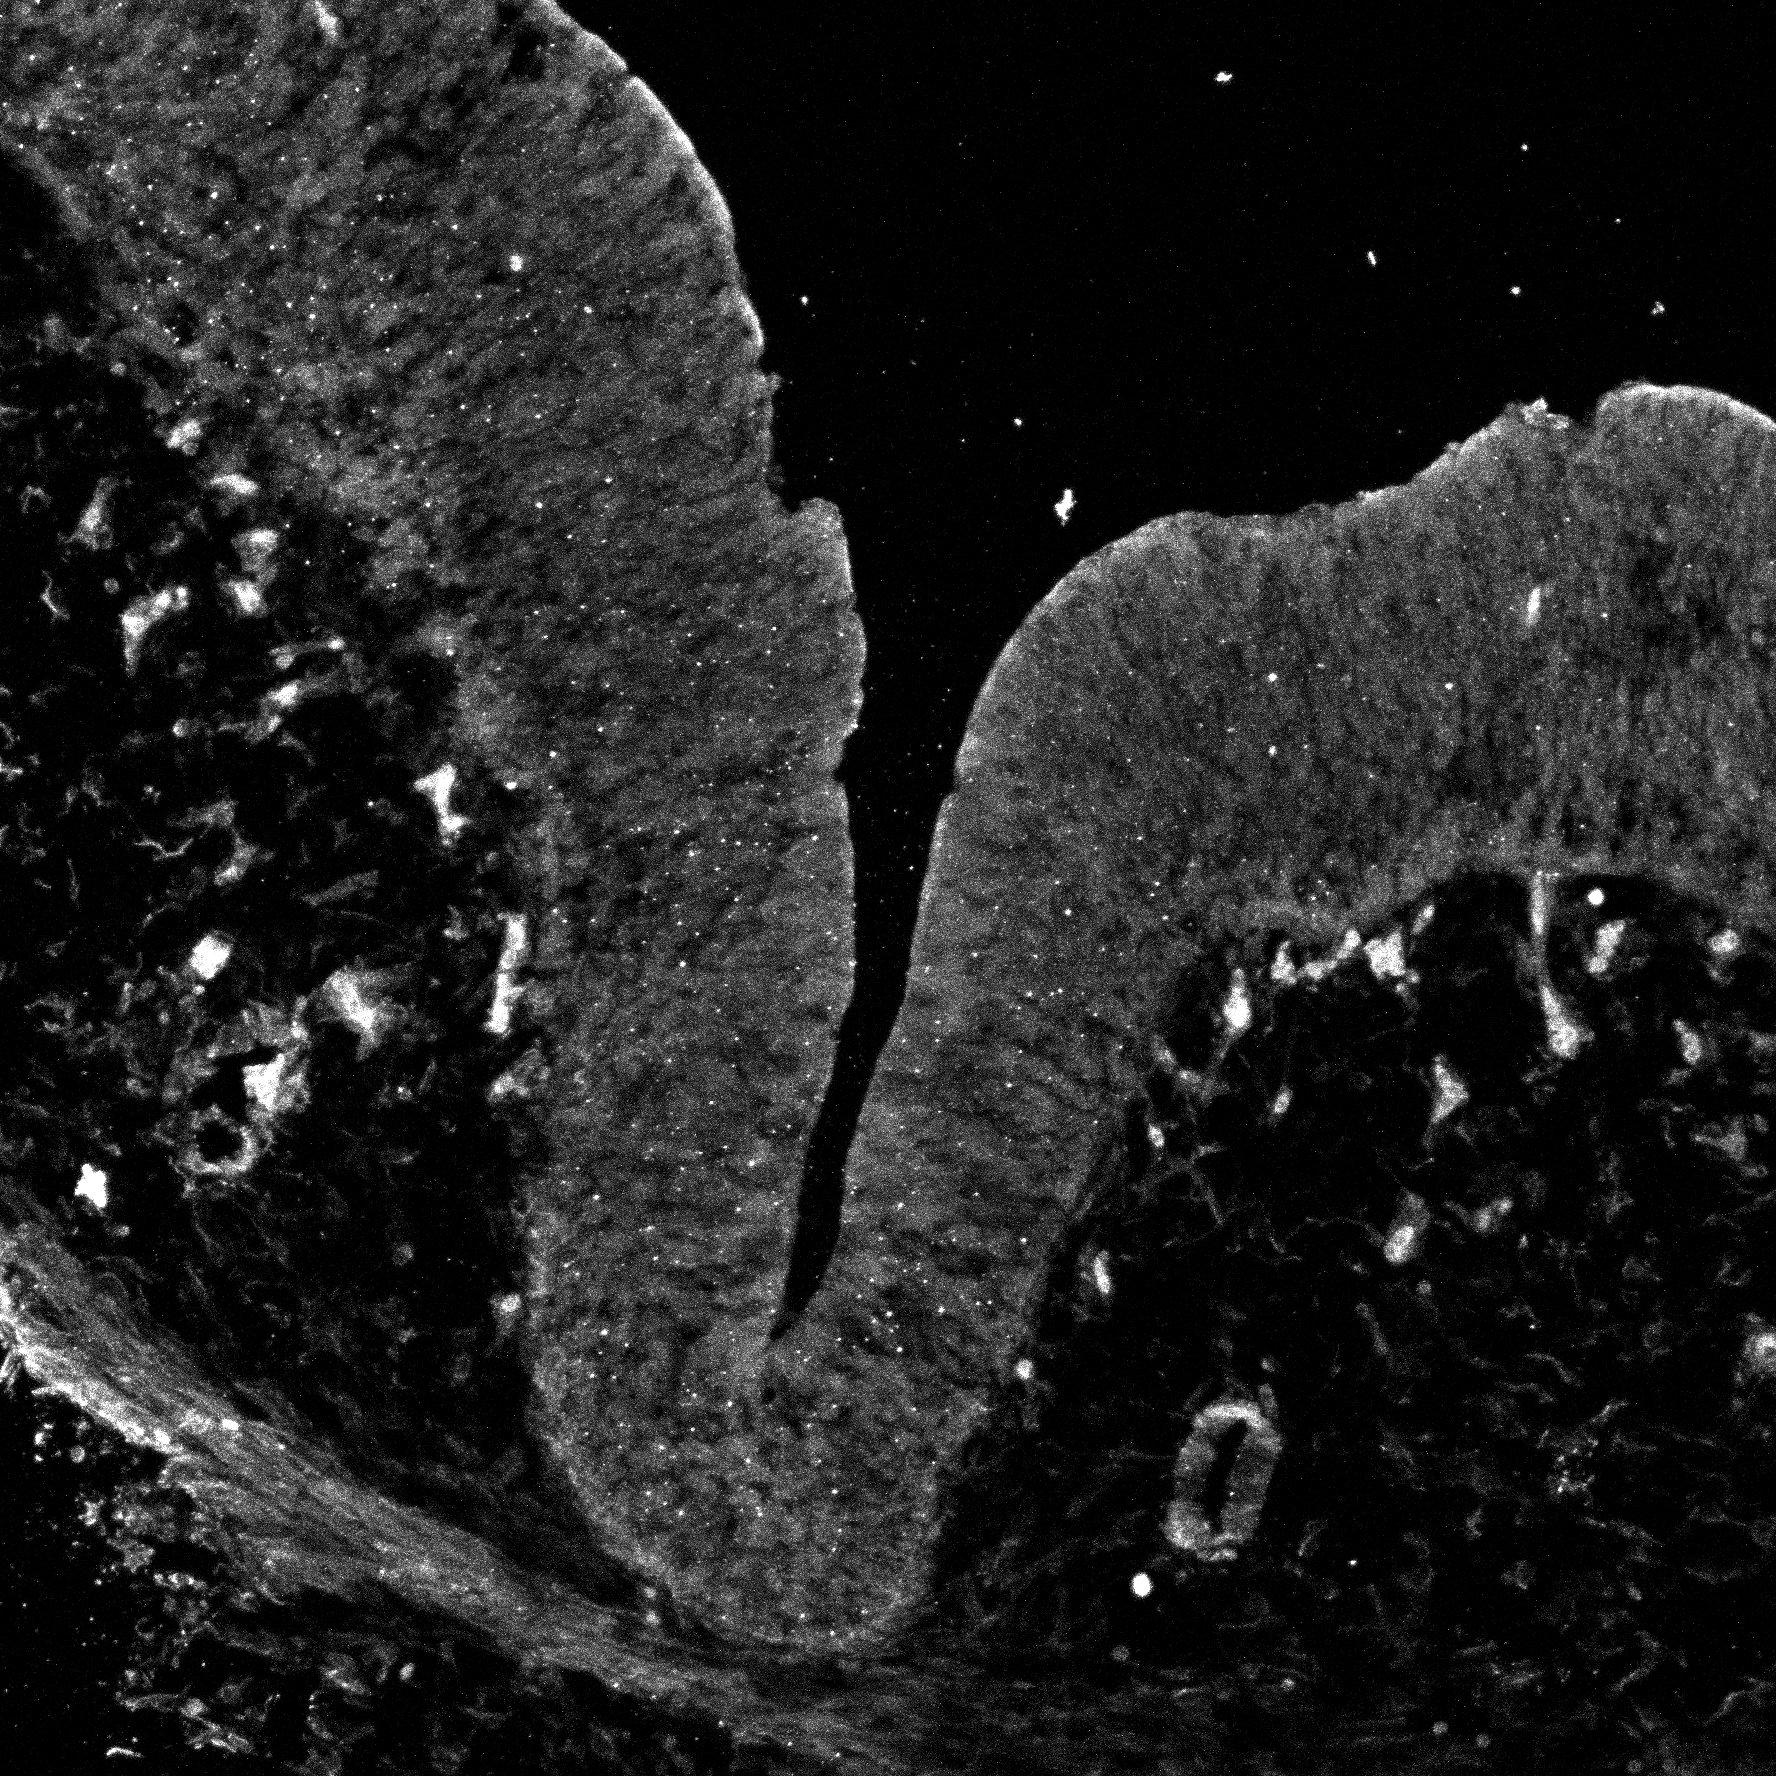

DAPI

11PCW human midbrain

MAP2

SOX2

Merged